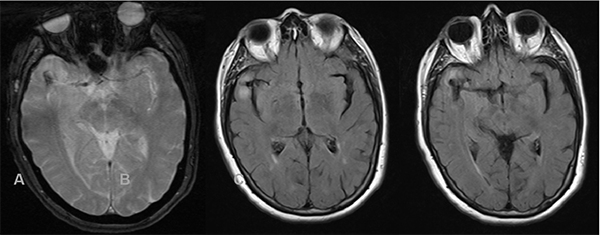

Figura 4:

Estudio por AD. Tanto en la imagen de la izquierda (vista anterior) y derecha (vista lateral) se observa a nivel silviano derecho dilatación aneurismática de contornos lobulados con diámetros aproximados de 10.7 x 9.7 mm.

Figura 5:

Estudio por AD, reconstrucción 3D del aneurisma descripto en Figura 4.